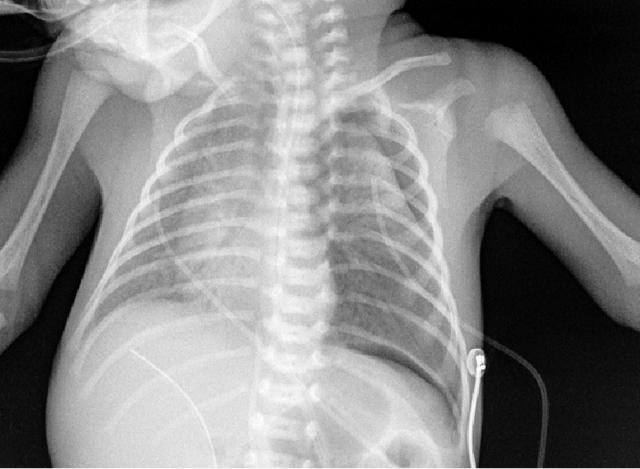

2、新生儿在剖腹产后数小时内出现呼吸困难。

仍可见双侧对称弥漫分布的的颗粒状高密度影,支气管充气征。

这就是典型的新生儿特发性呼吸窘迫综合征(RDS)。

其特征性 X 线表现为:

1)两肺野透光度普遍减低,呈毛玻璃状,或两肺野中内带多发细小颗粒状或小结节和网状影,下肺野较上肺野更为显著;

2)气管支气管充气显著,在两肺野密度普遍性增加的对比之下显示更为清楚;

3)胸廓扩张良好,横膈位置正常。 对怀疑本病者,短期(1 ~ 2h)连续拍片观察,对诊断意义较大;有文献提出凡 6~ 12h 胸部影像尚无确切网粒阴影者,可排除本病。